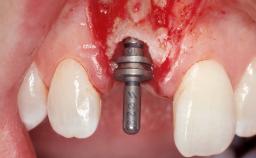

Late Placement of an Implant in a Maxillary Left Central Incisor Site

A 36-year-old female patient was referred for the replacement of the upper left central incisor (tooth 21), which had fractured. Although the tooth had been asymptomatic for many years, the crown began to loosen, at which time she presented to her dentist for an assessment. Teeth 21 and 22 had both been endodontically treated many years previously. She was a healthy individual and a non-smoker.

Bone Augmentation Horizontal|Staged

Augmentation Materials Xenogenous|Membrane

Soft Tissue Grafting Simultaneous

Bone Volume Deficient horizontally, requiring prior grafting